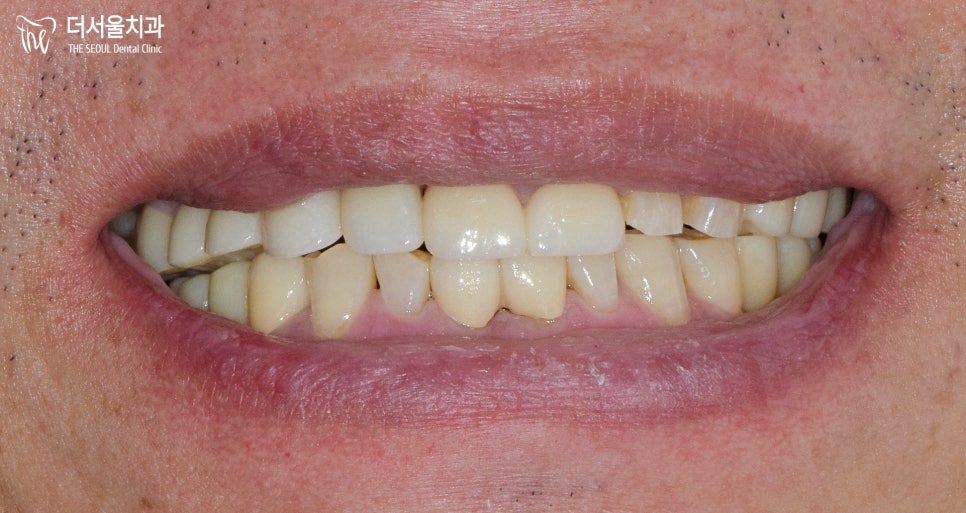

그리고 경과를 체크하러 오실 때

신경치료를 꼼꼼히 해드렸고

이를 확인할 수 있는 파노라마를 보면

근관충전이 뿌리끝까지 제대로

되어 있는 것을 볼 수 있습니다.ㅎㅎ

이후, 근관충전한 곳은 증상이 없는지

인공치근은 뼈와 잘 융합이 되었는지

확인한 다음 크라운 을 수복해 드렸습니다.

앞니를 회복하는 것은

기능 그 이상의 가치가 있습니다.

그러나 얼마 쓰지 못하고

다시 상태가 나빠진다면

그것은 하나 마나 한 치료가 되겠죠.

더서울에서는 단순히 1~2년,

눈에 보이는 것만 해결하는 것이 아닌

향후 10년 그 이상을 생각을 하며

신중하게 계획하고

진료해 드리고 있습니다.